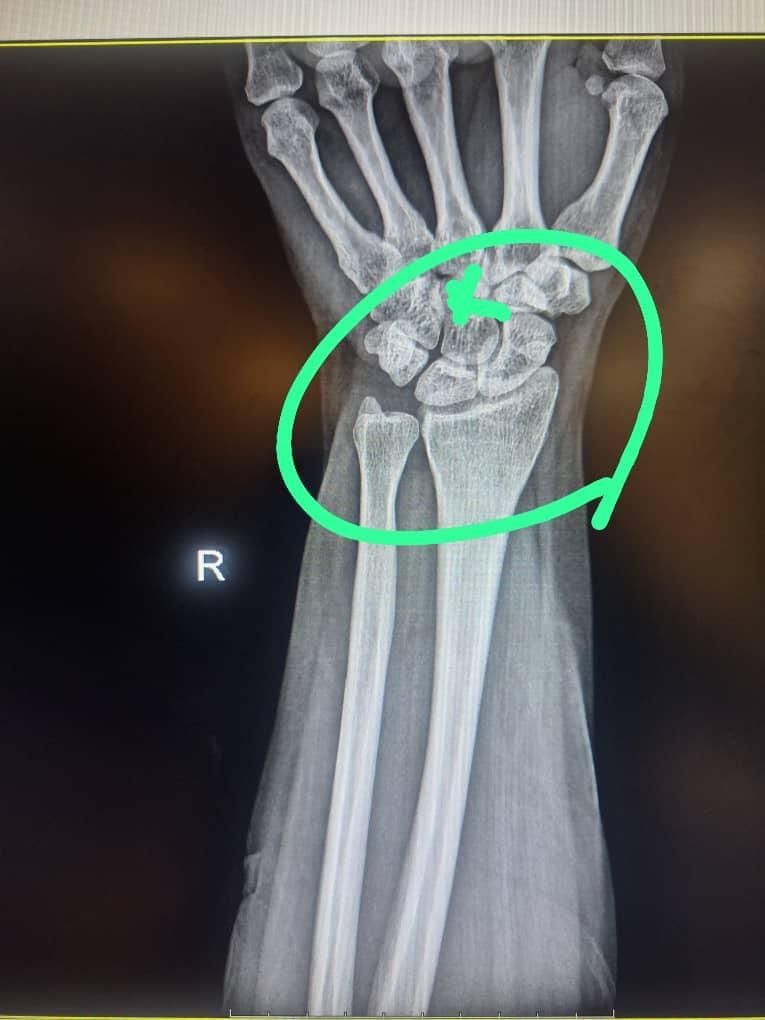

3. آموزش شکسته بندی و اصلاح مفاصل

آموزش شکسته بندی و اصلاح مفاصل

اموزش شکسته بندی اصلاح در رفتگی مفاصل جااندازی ناف تل گیری سق گیری تیکه اندازی اندازی اصلاح دنباچه اصلاح دیسک وسیاتیک مشکلات زانو ....

تصویر 1 از 1